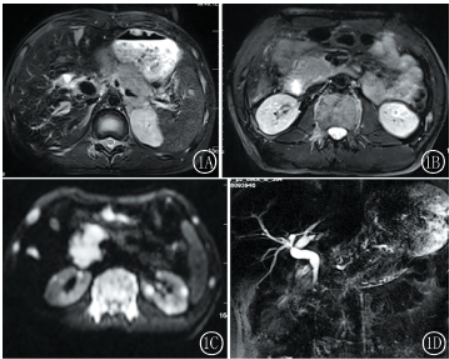

MRI上腹部检查(图1)示:胰腺弥漫性肿大,肝脏、双肾多发异常信号,T2呈稍高信号,DWI呈高信号,未见囊变、坏死;所示脊椎骨、胸廓组成骨DWI呈明显高信号;右中腹部肠管壁增厚,近端未见梗阻;MRCP示肝内外胆管未见明显梗阻。

图1A,1BT2WI示肝脏、胰腺、胃壁、左侧肾上腺病灶呈等高信号;图1CDWI示双侧肋骨、椎体、胰腺、双肾、肝脏病灶呈明显高信号;图1DMRCP示肝内外胆管未见扩张

结论:胰腺、肝脏、胃、双肾、右中腹部肠管、所示脊椎骨、及胸廓组成骨多发广泛异常信号,考虑为全身疾病所致,淋巴瘤不除外,建议进一步行PET-CT检查